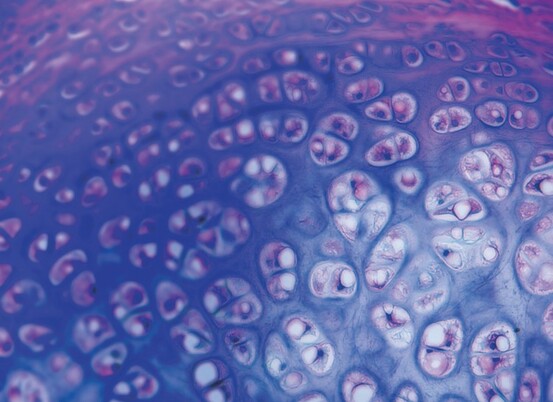

On appelle tissu conjonctif un tissu dont les cellules ne se touchent pas, mais sont plus ou moins éloignées les unes des autres par un mélange (la matrice extracellulaire) de molécules dissoutes, de fibres de structure, etc., le tout baignant dans ce qu’on appelle la substance fondamentale. Il s’agit du modèle de tissu le plus répandu dans le corps humain. Examinons d’un peu plus près l’ensemble de sa composition. La substance fondamentale est majoritairement formée d’eau, et sa consistance varie de quasi liquide à semi-gélatineuse. On y trouve différentes protéines et structures mi-protéiques mi-glucidiques (les glycosaminoglycanes), de l’acide hyaluronique et autres.

Les fibres de structure présentes sont au nombre de trois : le collagène, l’élastine et la réticuline. Le collagène (probablement la plus connue du grand public) est la protéine structurale la plus abondante dans notre organisme (environ un tiers du total des protéines), et il en existe de nombreux types, bien que les types 1, 2 et 3 prennent la quasi-totalité de l’ensemble. Formé d’une triple hélice, le collagène a un rôle de liaison, de soutien, de maintien, permet de " piéger " des molécules retenant l’eau (dans le ...